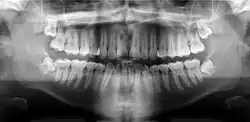

A dental panoramic radiograph, showing the maxilla and mandible, all the teeth including the "wisdom teeth," the frontal and maxillary sinuses, the nasal cavity and the temporomandibular joint and other near by head and neck anatomy.

A panoramic radiograph is a panoramic scanning dental X-ray of the upper and lower jaw. It shows a two-dimensional view of a half-circle from ear to ear. Panoramic radiography is a form of focal plane tomography; thus, images of multiple planes are taken to make up the composite panoramic image, where the maxilla and mandible are in the focal trough and the structures that are superficial and deep to the trough are blurred.